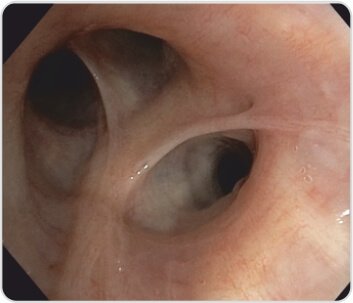

تُظهر الأشعة السينية للصدر اتساعًا فائقًا للمنصف. يُظهر التصوير المقطعي للصدر تضخم العقد اللمفية المنصفية مع عقدة مجاورة للرغامى العلوية اليمنى بقياس 2*3 سم، وتظهر حمة الرئة عقيدات انشطارية. تم إجراء EBUS TBNA تحت التخدير العام وكان اختبار ROSE (الفحص السريع في الموقع) إيجابيًا بالنسبة للالتهاب الحبيبي غير المسبب للحالة. تم إجراء تنظير القصبات في وقت واحد والذي أظهر وجود غشاء مخاطي عقيدي يوحي بوجود الساركويد.

الشكل 2: الغشاء المخاطي عقيدية